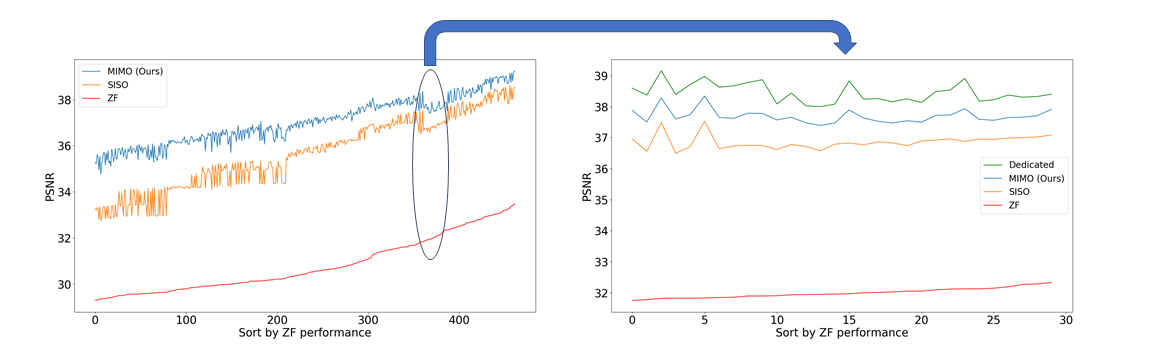

The study is done by training (i) one MIMO BRM, (ii) three SISO BRM for three sequences, and (iii) many models that are dedicated for specific sampling ratios. All the models follow the same structure as shown in Fig. 1. The proposed training scheme for continuous allows us to efficiently investigate the performance of different undersampling strategies. For each acquisition time setting , we search through possible on the following simplex: , which maximally utilizes the budgeted time . We select hundreds of under the 1:1:1 time setting, and set , or reduction in time. We run the trained models on the test set, and plot the reconstruction performances in Fig. 2. The top-three performing sampling strategies for different acquisition time setting are shown in Table 1.

Fig. 2 shows a clear performance gap between MIMO and SISO. Overall, the reconstruction performance of ZF images is the good indicator of the performances of BRMs; however, the correlation fluctuates often, and two sets of ZF that are similar in PSNR can swing for more than 1dB after going through BRM. To limit the number of dedicated models we need to train, we select a range of sampling factors of which ZF performance does not correlate well with MIMO/SISO performance, and train 30 dedicated models to see how well BRM predicts the performance of dedicated models.

As we observe from the right image in Fig. 2, our BRM, both from MIMO and SISO settings, predicts the performance of dedicated models with a high correlation. We further choose the best three , and perform the last stage of fine-tuning accordingly to (6). A visual evaluation on real data is shown in Fig. 3. For simulated data, please refer to the Supplemental Material section.